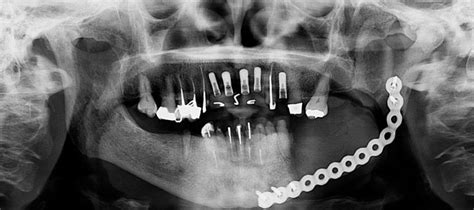

Se presenta el caso de una paciente de 84 años con osteoporosis, que presentó osteonecrosis mandibular tras la colocación de 6 implantes 5 meses después de la administración de denosumab. Una ortopantomografía y una TC mostraron pérdida ósea de la cresta mandibular y exposición ósea periimplantar.

Tras el tratamiento conservador con antibióticos y la suspensión de denosumab, se inició el tratamiento con teriparatida reduciéndose la infección del hueso necrótico y se observó nueva remodelación ósea. La patogénesis de la ONM por denosumab no está claramente definida, pero parece que la tasa del éxito de curación es superior a la ONM por bifosfonatos.

En este caso, la infección y la supuración desaparecieron con el tratamiento antibiótico descrito. Tras suspender la administración de denosumab e iniciar tratamiento con 20μg de teriparatida diarios en inyección subcutánea se observó con solo un mes de tratamiento una mejoría de todos los síntomas y una disminución en la extensión de las lesiones.